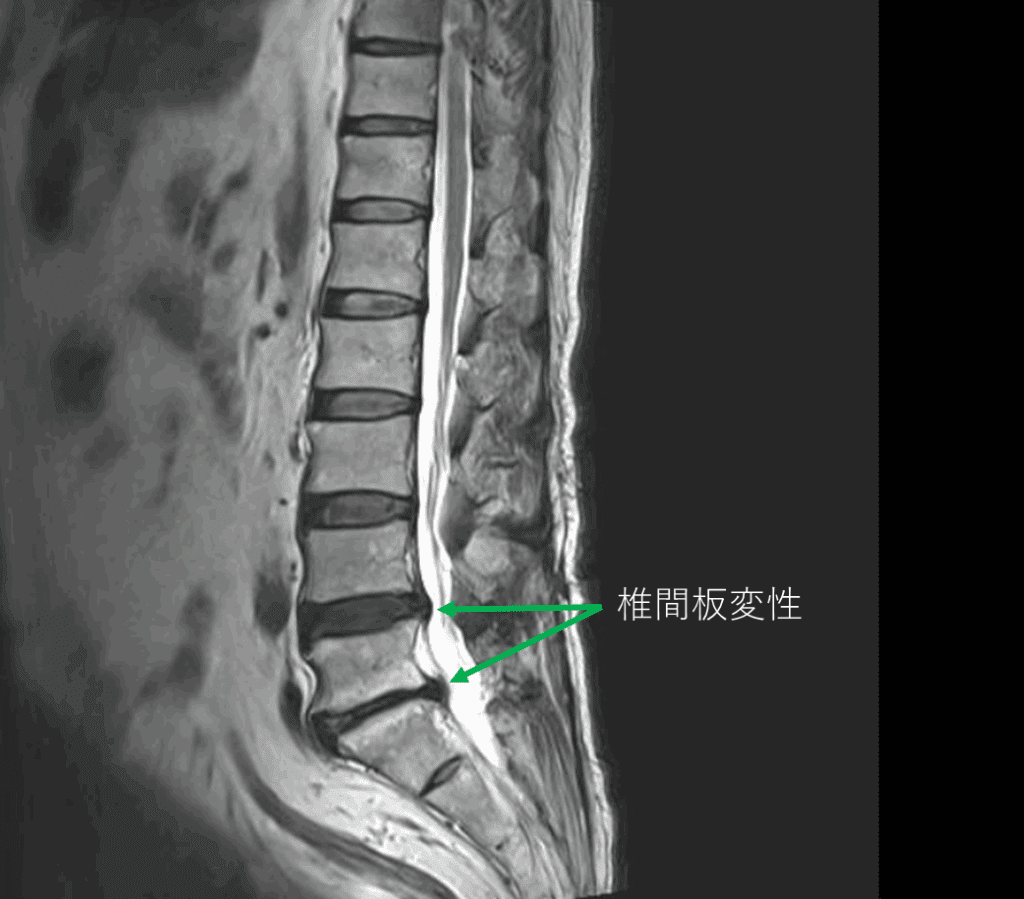

画像及び所見について

- L4/5,5/s-椎間板変性

- L4/5-椎間板ヘルニア

以上の事が画像上認められます。

・L4/5-椎椎間板ヘルニアを認め、主症状の原因の可能性が高い

・L5/s-椎間板変性による椎間孔狭窄を認め、主症状の原因の可能性がある